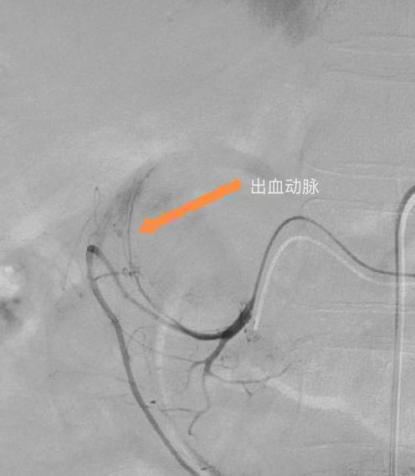

术中造影发现胃十二指肠一分支动脉渗血,随后应用栓塞剂进行栓塞,造影复查出血动脉未见显示,止血成功。术后患者症状改善,未再出现呕血、血色素上升,生命体征平稳。